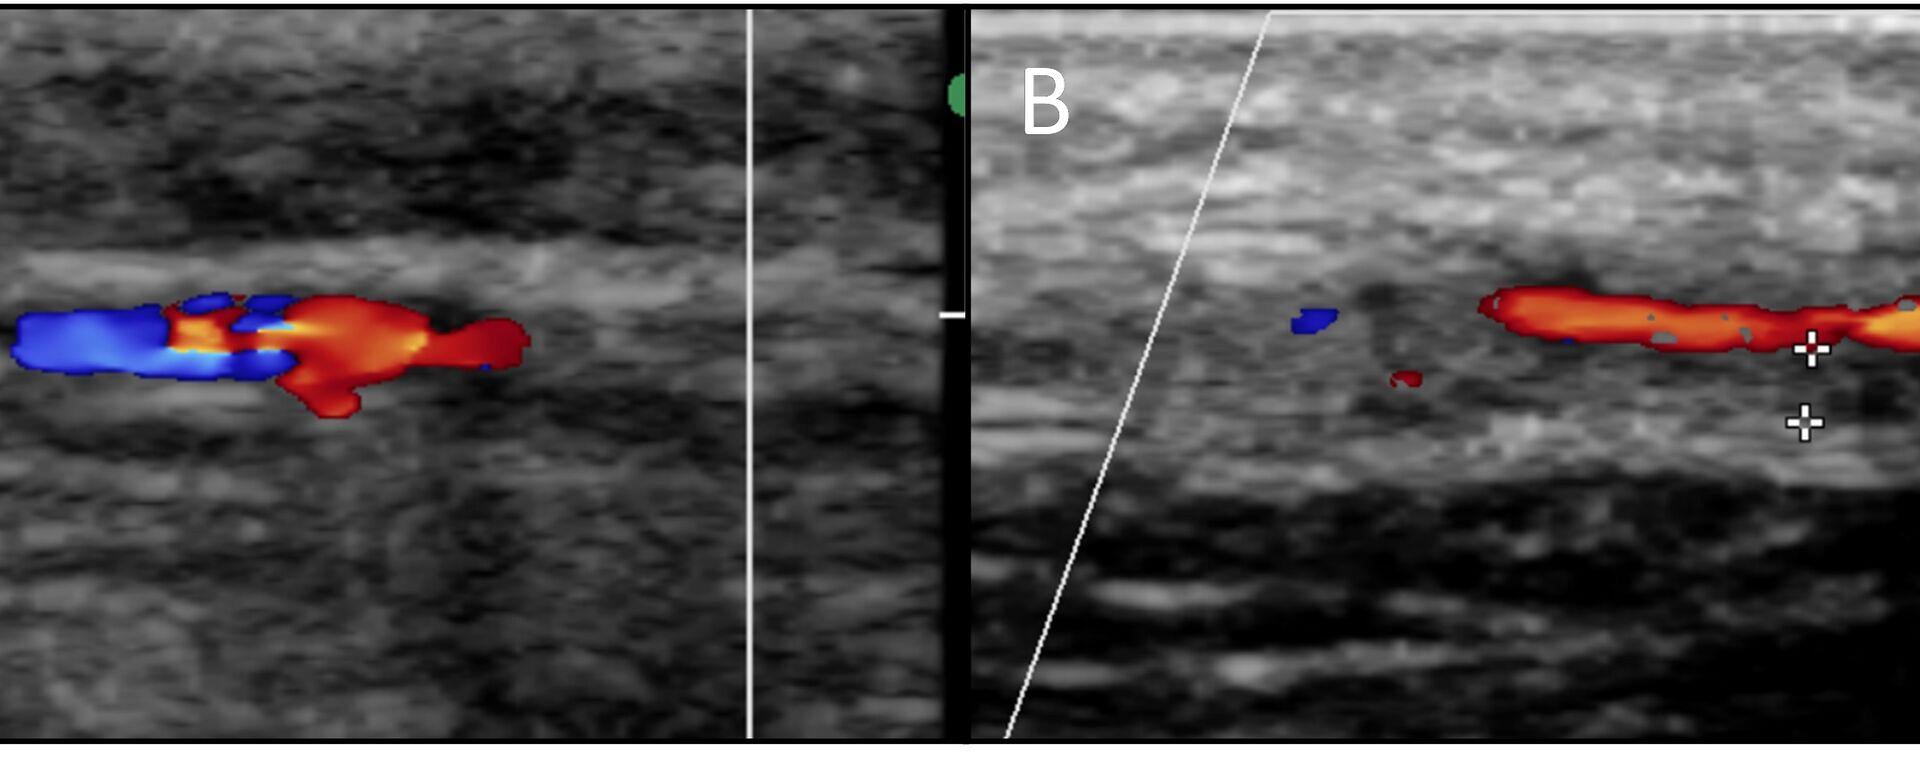

Vasculitis omvat een groep van ziektebeelden met de nodige overeenkomsten en verschillen. De klinische presentatie is vaak aspecifiek (fever of unknown origin) waardoor beeldvorming een belangrijke rol speelt bij de diagnostiek. Er is sprake van inflammatie in de vaatwand die zich uit in verdikking door oedeem, fibrosering en/of stenosering. Afhankelijk van het type vasculitis zijn er verschillende vaten betrokken en ook de mate van uitgebreidheid en ernst van het ziektebeeld zijn wisselend. Er zijn meerdere modaliteiten om vasculitis in beeld te brengen met elk hun voordelen en beperkingen. Dit artikel biedt achtergrondinformatie betreffende de vele vormen van vasculitis en aanverwante aandoeningen zoals polymyalgia rheumatica en retroperitoneale fibrose, doch met nadruk op vasculitis van de grote vaten. Tevens worden de uitingen van deze ziektebeelden op beeldvorming beschreven, met de nadruk op FDG-PET. Ten slotte zal monitoring van de therapierespons en follow-up kort aan bod komen.